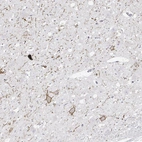

Immunohistochemical staining of human cerebral cortex, hypothalamus, lymphoid tissues and pancreas using Anti-CALCR antibody HPA028962 (A) shows similar protein distribution across tissues to independent antibody HPA061428 (B).